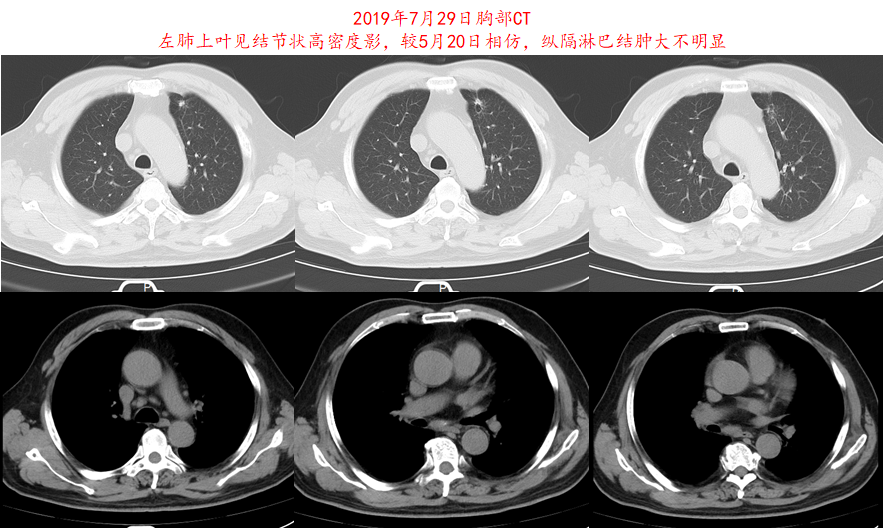

图6.患者2019年7月29日胸部CT影像资料